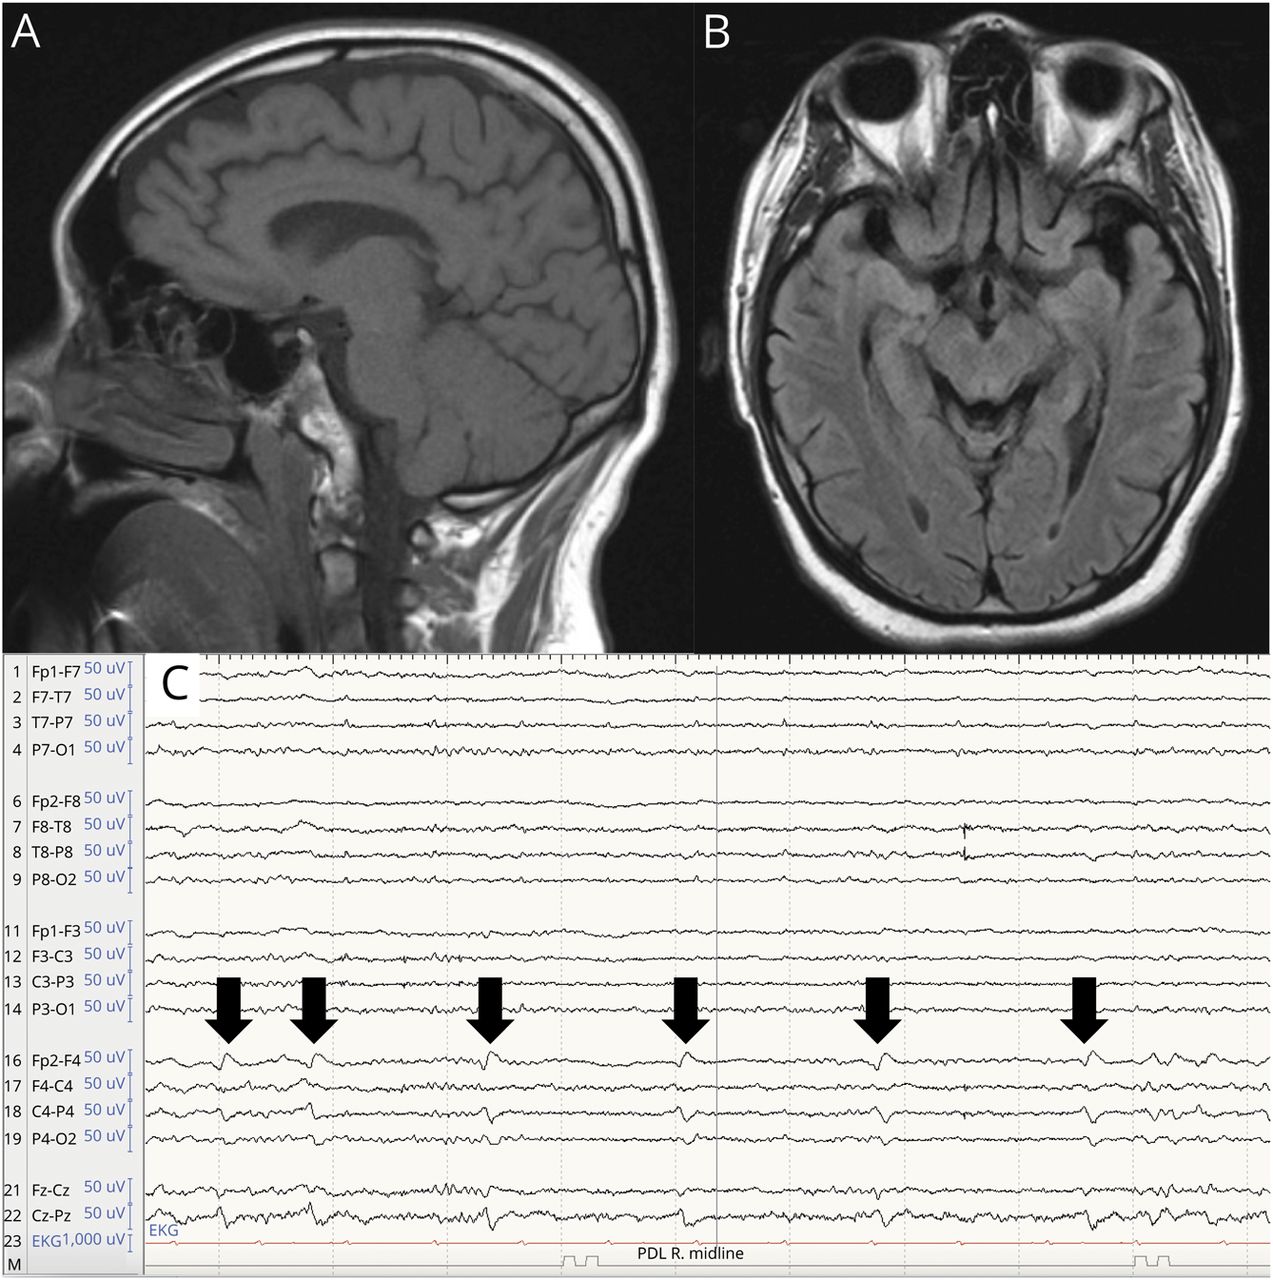

实验室基础检查结果为SARS-CoV-2阳性,伴淋巴细胞减少性白细胞减少。B12为462 pg/mL,叶酸>为20.0 ng/mL。尿酸6.8 mg/dL(2.3-7.6,正常)。脑部核磁共振造影显示皮质萎缩(图1),但没有其他急性症状,颈椎核磁共振成像(未显示)无明显症状。连续脑电图(cEEG)监测48小时,表现为广泛性连续δ慢活动,并叠加较快频率。脑脊液研究显示正常的细胞计数,蛋白质,葡萄糖,IgG合成率/指数,和阴性脑膜炎面板。依次进行脑病、自身免疫、血清和脑脊液检查。考虑到患者的年龄和最近发生的痛风和肾功能不全,发送尿液氨基酸分析。

A)脑矢状t1加权MRI和B)脑轴向T2/FLAIR MRI显示皮层萎缩;C)连续视频脑电图记录样本显示右侧额中央区域的偏侧周期性放电(黑色箭头),与诱发癫痫的潜在区域一致。

在成人发病形式中,神经病变或脊髓病是最常见的临床症状,其次是共济失调或构音障碍、认知能力下降、精神症状、下肢无力和癫痫。其他特征包括血栓栓塞性疾病和肾衰竭,通常是由于血栓性微血管病(TMA)的损害。7,14我们的患者最终出现急性双侧上肢头静脉血栓和右下叶节段性肺栓塞,为此他开始接受治疗性抗凝。他也有肌酐升高(峰值3.6-3.8 mg/dL),但其肾脏疾病的确切病因尚不清楚,并且他没有TMA的其他伴随体征(无高血压、血尿或蛋白尿)。肾活检被推迟,因为它不太可能改变治疗和抗凝治疗的风险增加。此外,他的病程因临床癫痫伴左凝视偏移和全身性惊厥而复杂化。患者再次接受脑电图检查,结果显示右侧额中央偏侧性周期性癫痫样放电和癫痫发作,但无明确的临床相关性,并开始服用抗癫痫药物。最后,痛风通常与嘌呤代谢的先天性代谢错误有关,也有甲基丙二酸血症的病例报道,可能与肾脏尿酸清除率降低有关。3.